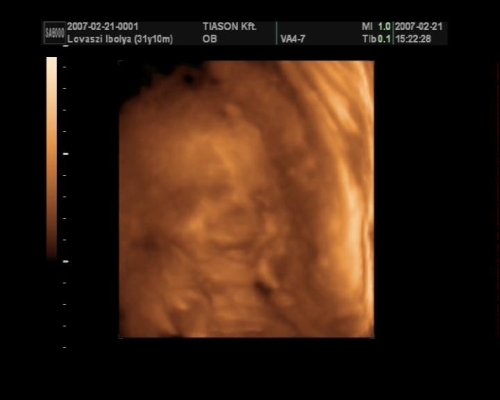

, de ami fura volt, a szívét a pocakom bal oldalán középtájban éreztem, felette pedig folyamatos rugdosást, vagy kalimpálást, De a másik oldalon ugyanott szintén... Lehet, hogy keresztben van???? De a múltkor már lent volt. Na kíváncsi vagyok kedden mit mutat az UH. Dehát azt csak lehetne látni rajtam, ha keresztben lenne...